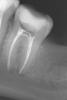

natalia sado Опубликовано 3 ноября, 2012 Поделиться Опубликовано 3 ноября, 2012 Здравствуйте. Моя ситуация такова: зуб 37 был пролечен летом, нерв не трогали, поставили пломбу. Но! впоследствии появилась боль при накусывании (т.е. жить мне он не мешал, болеутоляющие я не пила, но понимала, что корочку хлеба он жевать не может. Иду к врачу, говорит: "я знал, потому как пульпа была слишком близко, пожалел тебя и зуб, а надо было депульпировать" Что он и сделал. (см снимки 1 и 2). Также он решил, что нужен штифт, но это позже, нужно чтобы прошло время. Время это как раз нам было очень на руку, потому как сразу от него я пошла в кабинет хирурга удалять соседнюю восьмерку,от которой накакуне просто отвалился кусок. Я еще помню подумала, что может оно как-то не очень сочетать эндодонтическое лечение и удаление соседнего зуба, тем более что зуб мудрости был ого-го!! а удалял мне его хирург 1.5 часа (врач кстати отличный), но возможно это всего лишь женская привычка все преувеличить Пошла я восвояси заживлять лунку, с временной пломбой на 37 зубе, ожидающего штифта и реставрации. Дело было 9 сентября.В 20х числах сентября я была на осмотре у хирурга, т.к. восьмерка у меня заживать не хотела, промучилась я с осложнениями, но не так все просто - опять напасть: За это время замечала снова болевые ощущения на этой 7ке, пробовала пожевать, когда лунка позволила-те же симптомы, все точно также, опять на грубую пищу такая реакция (надо сказать, что эта симптоматика вообще стала мне родной за последнее время, это был не первый зуб со схожими проблемами). Тут же заруливаю к своему лечащему. Сделали снимок (3), посовещался с коллегами- все в один голос: неееееет!!! не может быть!! чему тут болеть, запломбировано все идеально, это оседает материал. ну ок! только вот неделю назад надоело мне ждать, пока "он осест" и я пошла с твердым намерением сделать снимок (кстати действительно настояла, опять пытались переубедить).И вот результат: фото 4! даже я вижу, с каналами то проблема!! уже и мой врач не отрицает , но хотелось бы понять, судя по динамике снимков, что же произошло, почему, и что тут теперь вытворять?Пожалуйста, выскажитесь, очень важны ваши советы и мнения. Уже обращалась к вам недавно по поводу синуслифта, помогли настроиться и принять решение. Очень не хочется вслепую вершить судьбу своих зубов. Ссылка на комментарий

natalia sado Опубликовано 3 ноября, 2012 Автор Поделиться Опубликовано 3 ноября, 2012 Вот только фото разместились четко наоборот))Чтобы соблюсти хронологию снимков, отсчет по номерам, кот. я указала в тексте, ведем справа налево Ссылка на комментарий

Magdalena Опубликовано 3 ноября, 2012 Поделиться Опубликовано 3 ноября, 2012 За период от первого до последнего снимка на корнях появилось воспаление. Причины могут быть 1. Погрешности в обработке каналов, лечение без изоляции зуба коффердамом ( могла слюна попасть с микробами) 2..Впечатление, что на снимке с инструментами в дистальном корне (ближе к 8 зубу) есть еще один канал. Уточнить до перелечивания можно сделав 3д-томограмму. Ссылка на комментарий

ger_berra Опубликовано 12 ноября, 2012 Поделиться Опубликовано 12 ноября, 2012 Я вижу в Вашем зубе апикальную перфорацию.Это ложный ход корневого канала,который делается инструментом .Не нарочно,конечно.Таким образом в очень важной части канала("верхушка") осталась органическая ткань("нерв"),к которой присоединились микроорганизмы из слюны,которые её кушают.Обработка проводилась без коффердама,так что запросто могло "натечь в зуб".Если зуб дорог,то его нужно полностью "перебрать",отмыть,с временной пломбировкой гидроксидом кальция и плотной постоянной пломбировкой. 1 Ссылка на комментарий